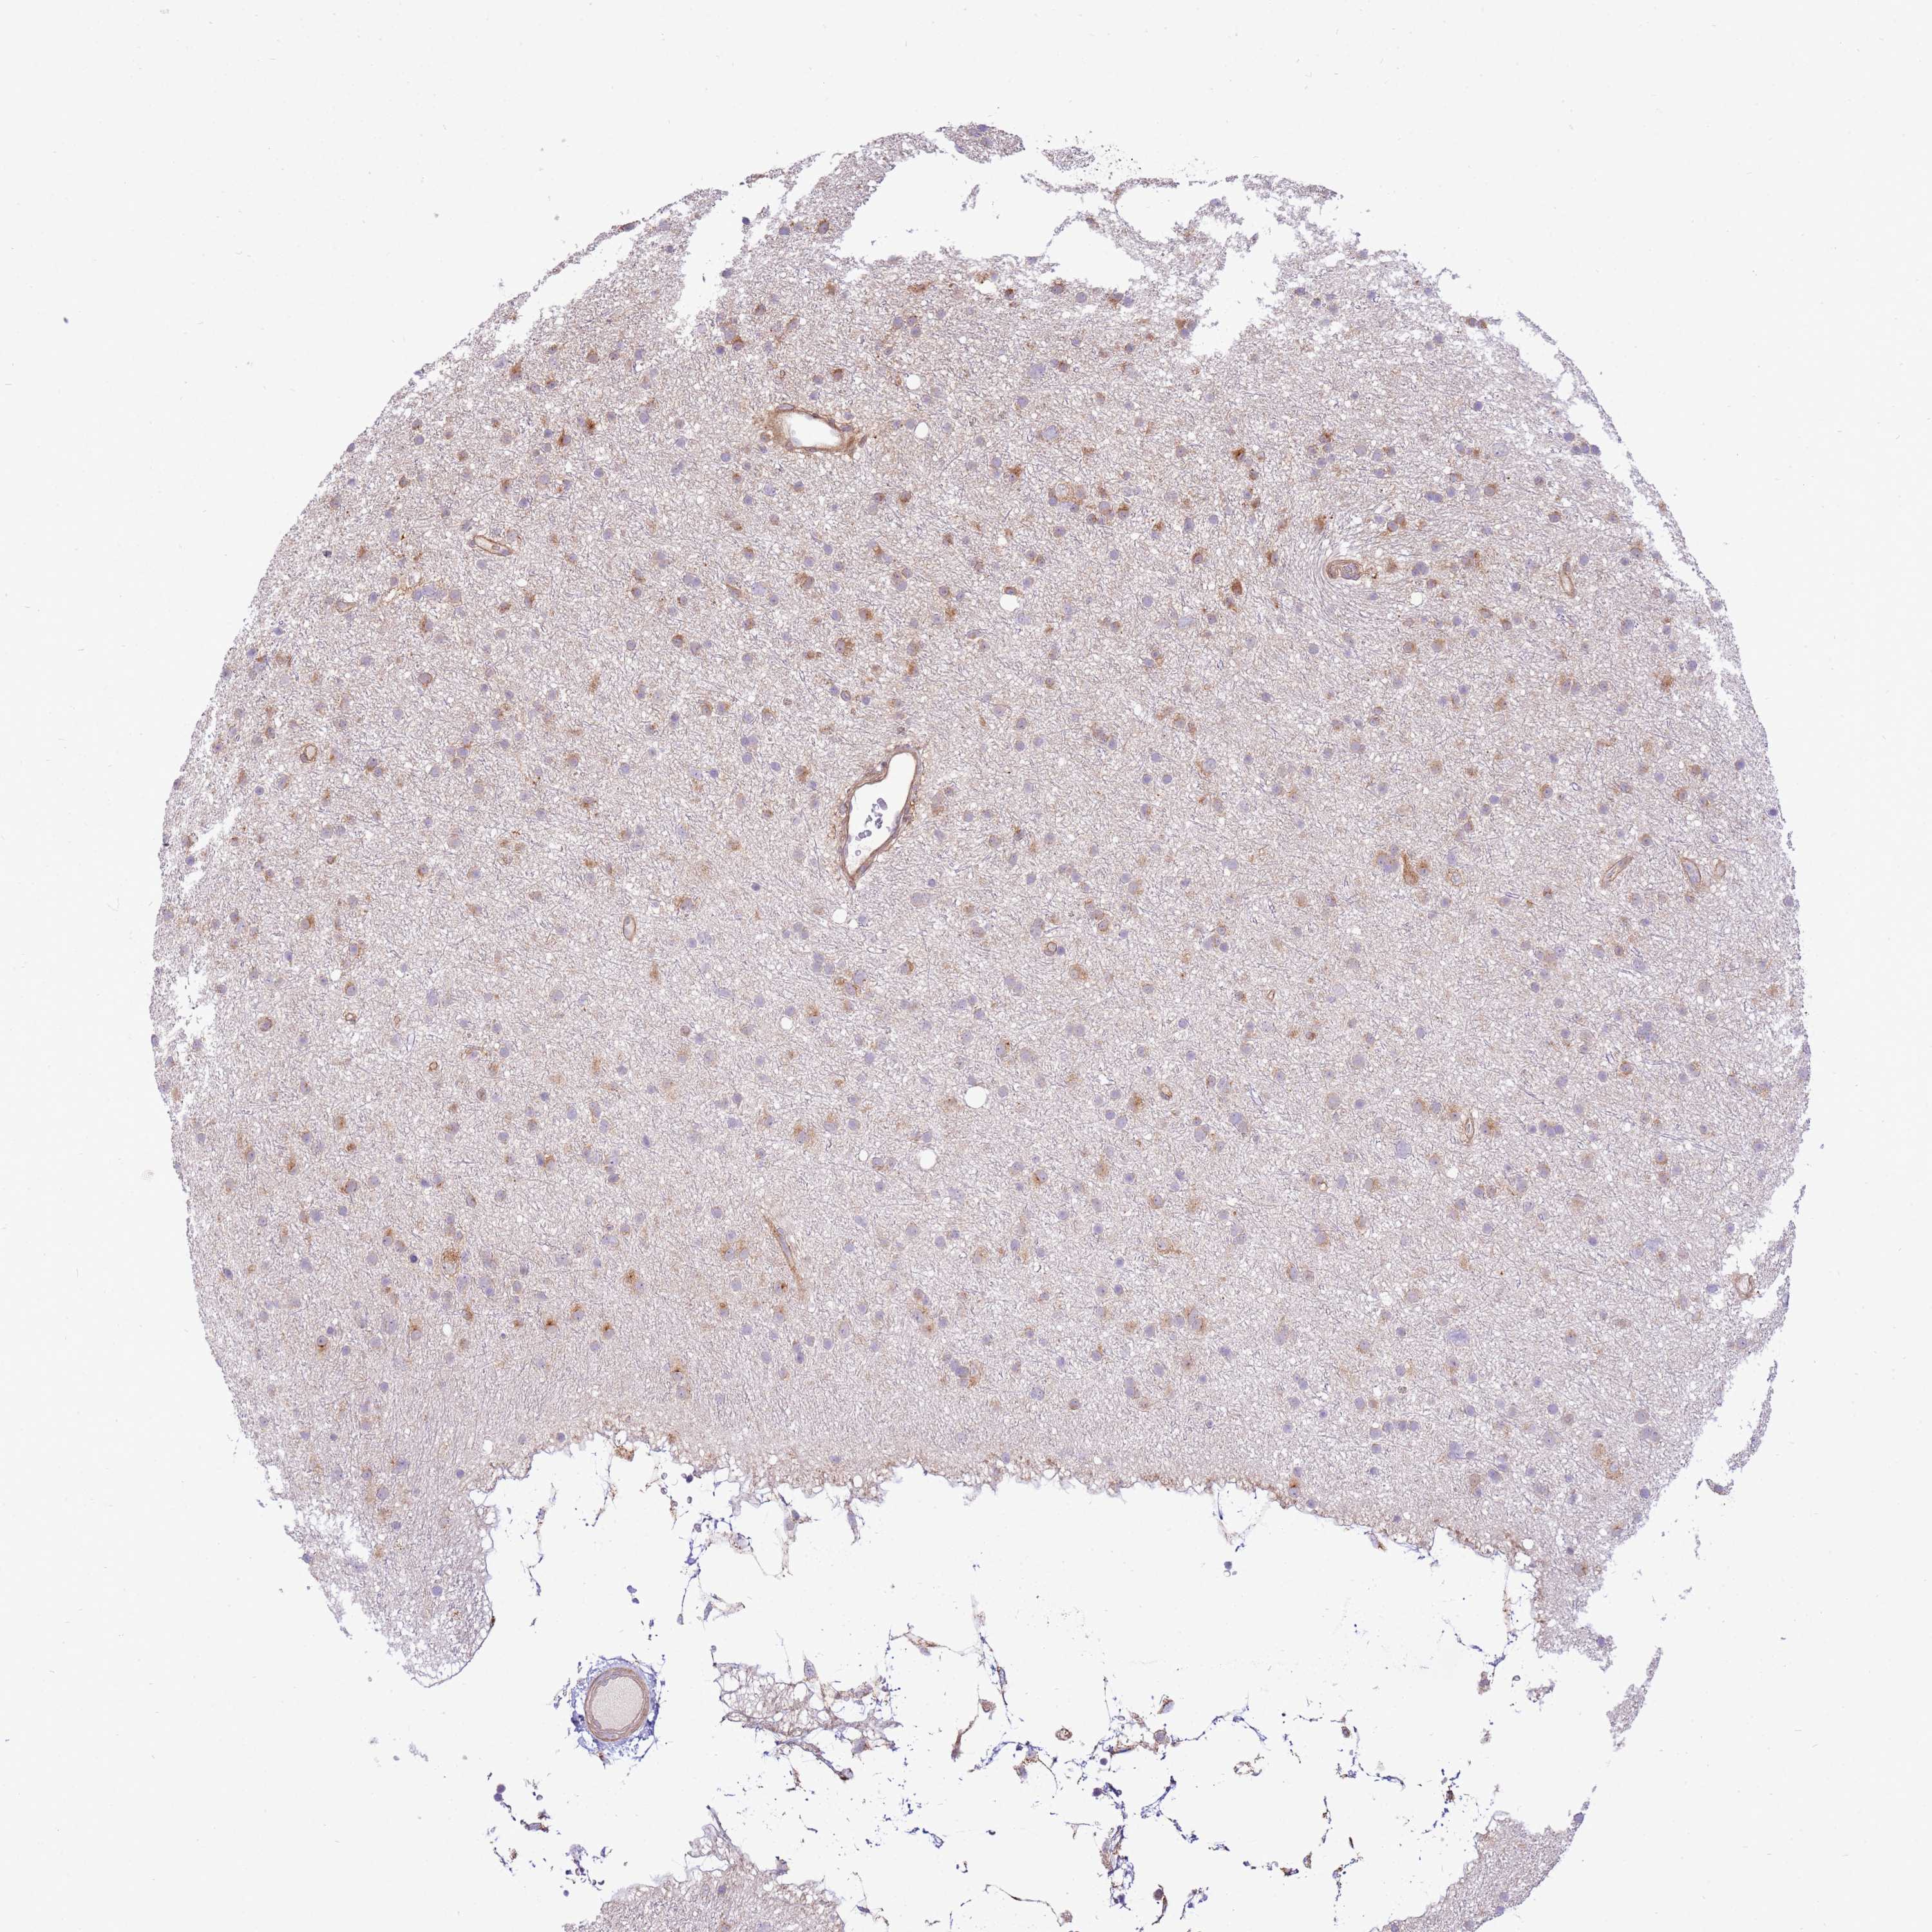

GLIOMA - Protein expressioni

A mouse-over function shows sample information and annotation data. Click on an image to view it in a full screen mode. Samples can be filtered based on level of antibody staining by selecting one or several of the following categories: high, medium, low and not detected. The assay and annotation is described here.

Note that samples used for immunohistochemistry by the Human Protein Atlas do not correspond to samples in the TCGA dataset.

Antibody stainingi

Antibody staining in the annotated cell types in the current human tissue is reported as not detected, low, medium, or high, based on conventional immunohistochemistry profiling in selected tissues. This score is based on the combination of the staining intensity and fraction of stained cells.

Each image is clickable and will lead to virtual microscopy that enables deeper exploration of all samples and also displays staining intensity scores, fraction scores and subcellular localization as well as patient and tissue information for each sample.

Antibody HPA047386

Staining

High

Medium

Low

Not detected

Intensity

Strong

Moderate

Weak

Negative

Quantity

>75%

75%-25%

<25%

None

Location

Nuclear

Cytoplasmic/membranous

Cytoplasmic/membranous,nuclear

Glioma, malignant, High grade

Glioma, malignant, Low grade